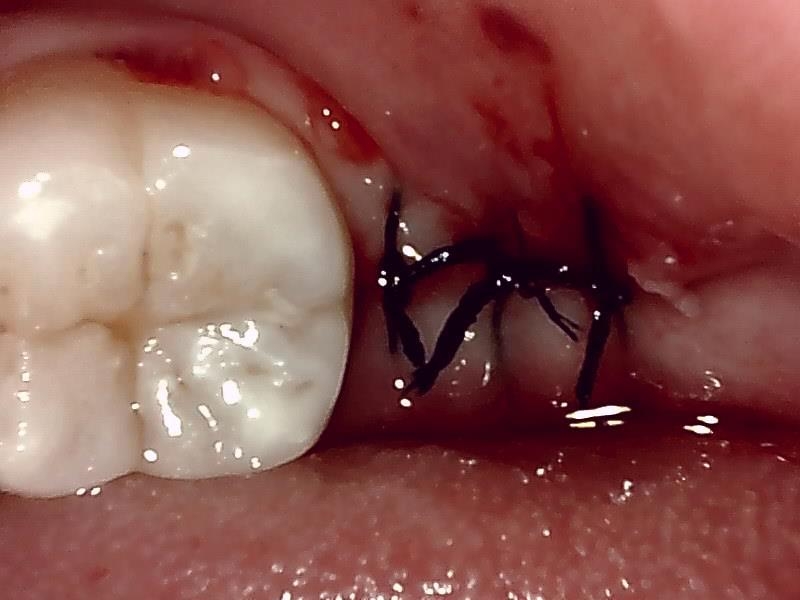

縫合

治癒

当院では、傷口は最小限に、骨は極力削らずに行います。

骨が歯を覆っているケース以外は骨を削ることはありません。

親知らずのみにアプローチし歯を分割し最小限の傷口で取り出します。

歯肉を切開し、歯が見えるようにして、

周辺の骨を削らないように親知らずを分割し抜きやすくしていきます。

この抜歯法により術後の腫れ痛みが大幅に軽減されます。

抜歯後、経過良好です。